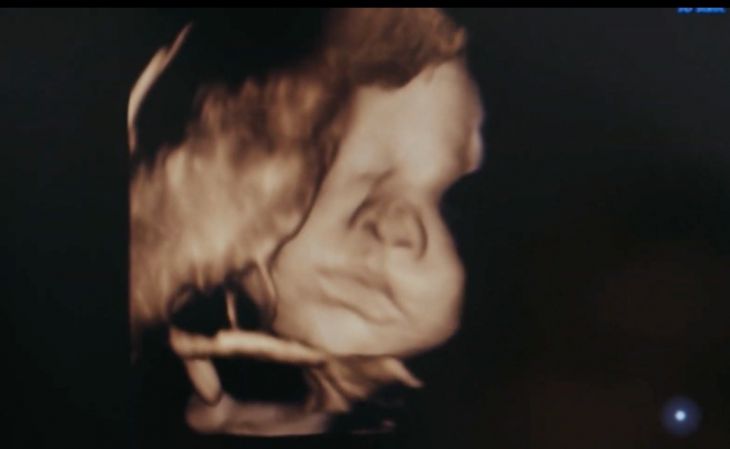

Especialistas de la UNAM, la Universidad Autónoma de Metropolitana (UAM) y del Instituto de Perinatología desarrollan un software de inteligencia artificial para conocer el estado de salud de los bebés antes de nacer, que sería capaz de funcionar a distancia.

El objetivo es que los ginecólogos de localidades lejanas puedan tomar imágenes del ultrasonido de un feto y las envíen al Instituto de Perinatología, en la Ciudad de México, donde se analizarán con un sistema automático para detectar si existen alteraciones.

“La idea es, a través del análisis de imágenes, producir un diagnóstico. Por ejemplo, irrigación sanguínea en el cerebro fetal, con imágenes de ultrasonido dopler que miden directamente el flujo de sangre en el cerebro y el software lo analiza, se hace un estimado y se puede hacer una comparación del flujo normal contra algo anormal, que ya el experto o la experta recomendará”, detalló Fernando Arámbula Cosío, del Instituto de Investigaciones en Matemáticas Aplicadas y en Sistemas a través de Gaceta UNAM.

El Sistema automático para apoyo en la evaluación, clasificación y asignación de riesgos en fetos con alteraciones en crecimiento funciona con algoritmos de inteligencia artificial que podrán estimar si un bebé se encuentra sano.

El programa revisará el tamaño del fémur, la circunferencia craneal, interpretará las contracciones del corazón del feto, entre otras características.